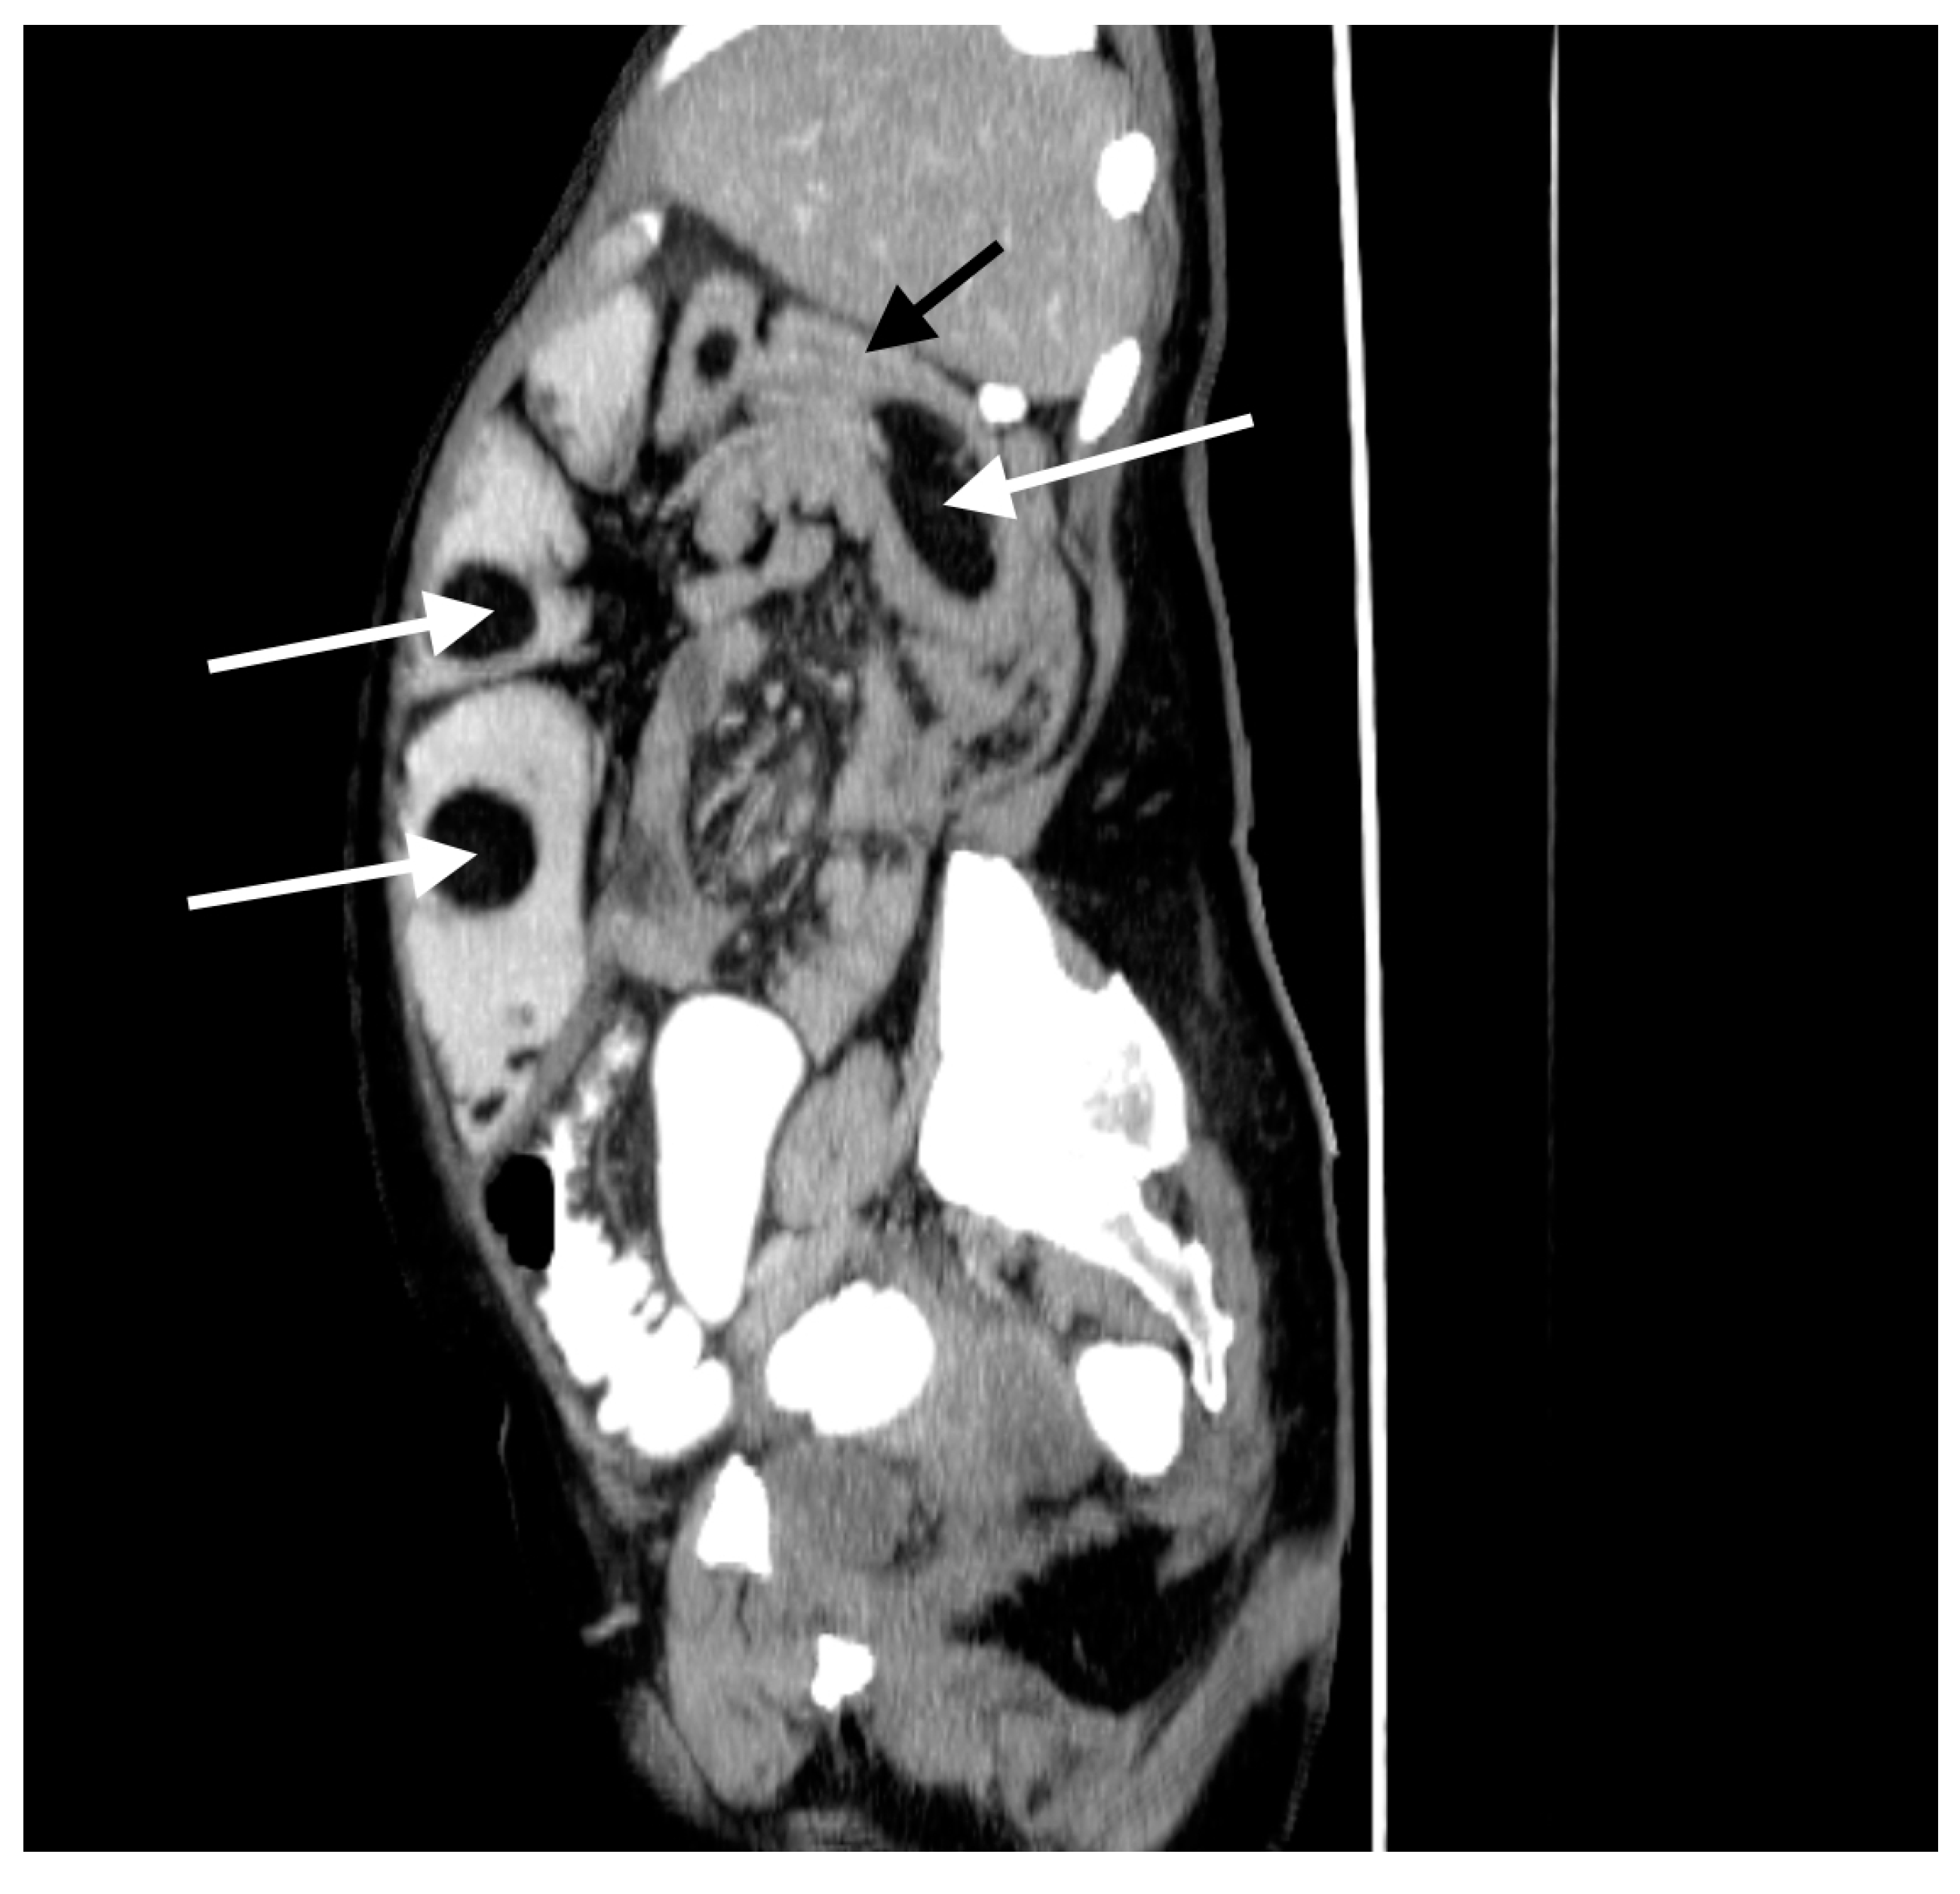

A 60-year-old woman was admitted to the emergency department complaining of acute abdominal pain, vomiting and diarrhea. Her medical history included appendectomy in childhood, hysterectomy, hepatic steatosis, chronic kidney disease (CKD) and chronic malnutrition with iron deficiency. She has also been treated for indeterminate inflammatory bowel disease (she reported taking sulfasalazine, 1.0 g three times daily) and had a twenty-year history of recurrent abdominal pain accompanied by a feeling of fullness and abdominal distension. Twenty-six years prior to admission, she underwent surgery for ileus and a large polyp in the ileum was locally resected. The patient did not provide documentation from her previous hospitalizations in other wards. Physical examination revealed absence of bowel sounds and generalized abdominal tenderness. Laboratory tests showed mild anemia and low serum protein level. Abdominal CT scan demonstrated small bowel distension (Figure 1) with ileo-ileal intussusception caused by one of multiple pedunculated lipomatous polyps arising from the mesenteric border of the jejunum (Figure 1 and Figure 2). Multiple giant diverticula were also visualized (Figure 1 and Figure 3).

Figure 2.

Contrast-enhanced CT image of the abdomen and pelvis, sagittal section. Multiple jejunal lipomas (white arrows) and intussuscepted jejunum with a lipoma as the leading point (black arrow).